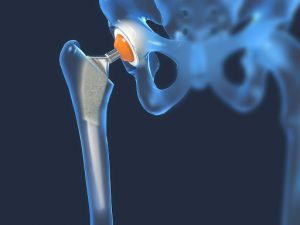

Conclusiones del estudio HEALTH

Recientemente participamos en el estudio HEALTH, cuyo objetivo principal era evaluar el impacto de una artroplastia total de cadera comparada con una hermiartroplastia, en relación a sus procedimientos quirúrgicos para